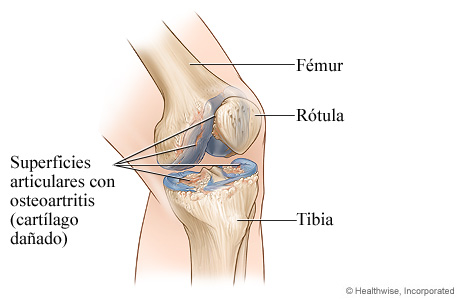

Osteoartritis de la rodilla

En la osteoartritis, el cartílago que protege y amortigua las articulaciones se deteriora con el tiempo. A medida que el cartílago se desgasta, las superficies óseas se frotan entre sí. Esto daña el tejido y el hueso, que luego causa dolor. La osteoartritis es común en las articulaciones de la rodilla.